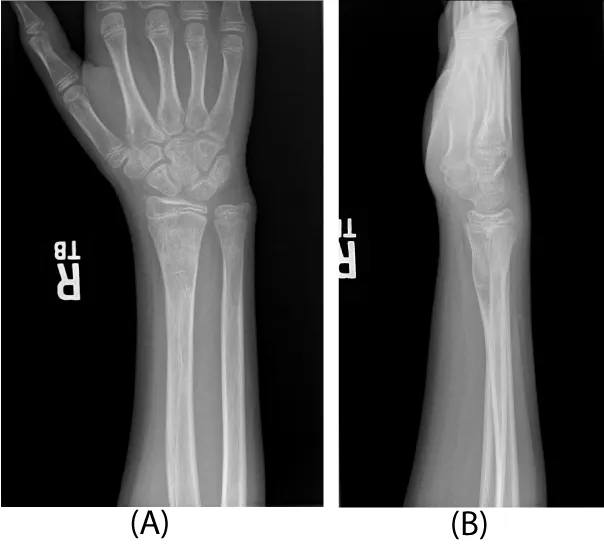

An 11 year-old right-hand-dominant healthy male presented after sustaining an isolated injury to his right wrist while snowboarding two days prior. The patient was seen at an outside emergency room and a splint was applied without manipulation. On examination, he had a normal neurovascular exam and full digital motion. An obvious clinical deformity was present. Radiographs of the right wrist revealed an extra-articular, extra-physeal distal radius fracture with dorsal angulation.

Three days after injury, consent was obtained, and the patient was taken to the operating room. There he underwent a manipulative closed reduction. Once reduction was obtained, percutaneous pin fixation was utilized to stabilize the fracture. Under flouroscopic guidance, two smooth 0.062 inch Kirschner wires were placed into the radial styloid tip and across the fracture site (Figure 2). Both pins were placed uneventfully with one attempted insertion. There were not multiple passes. The patient was then placed in a short arm cast that was split in the operating room.